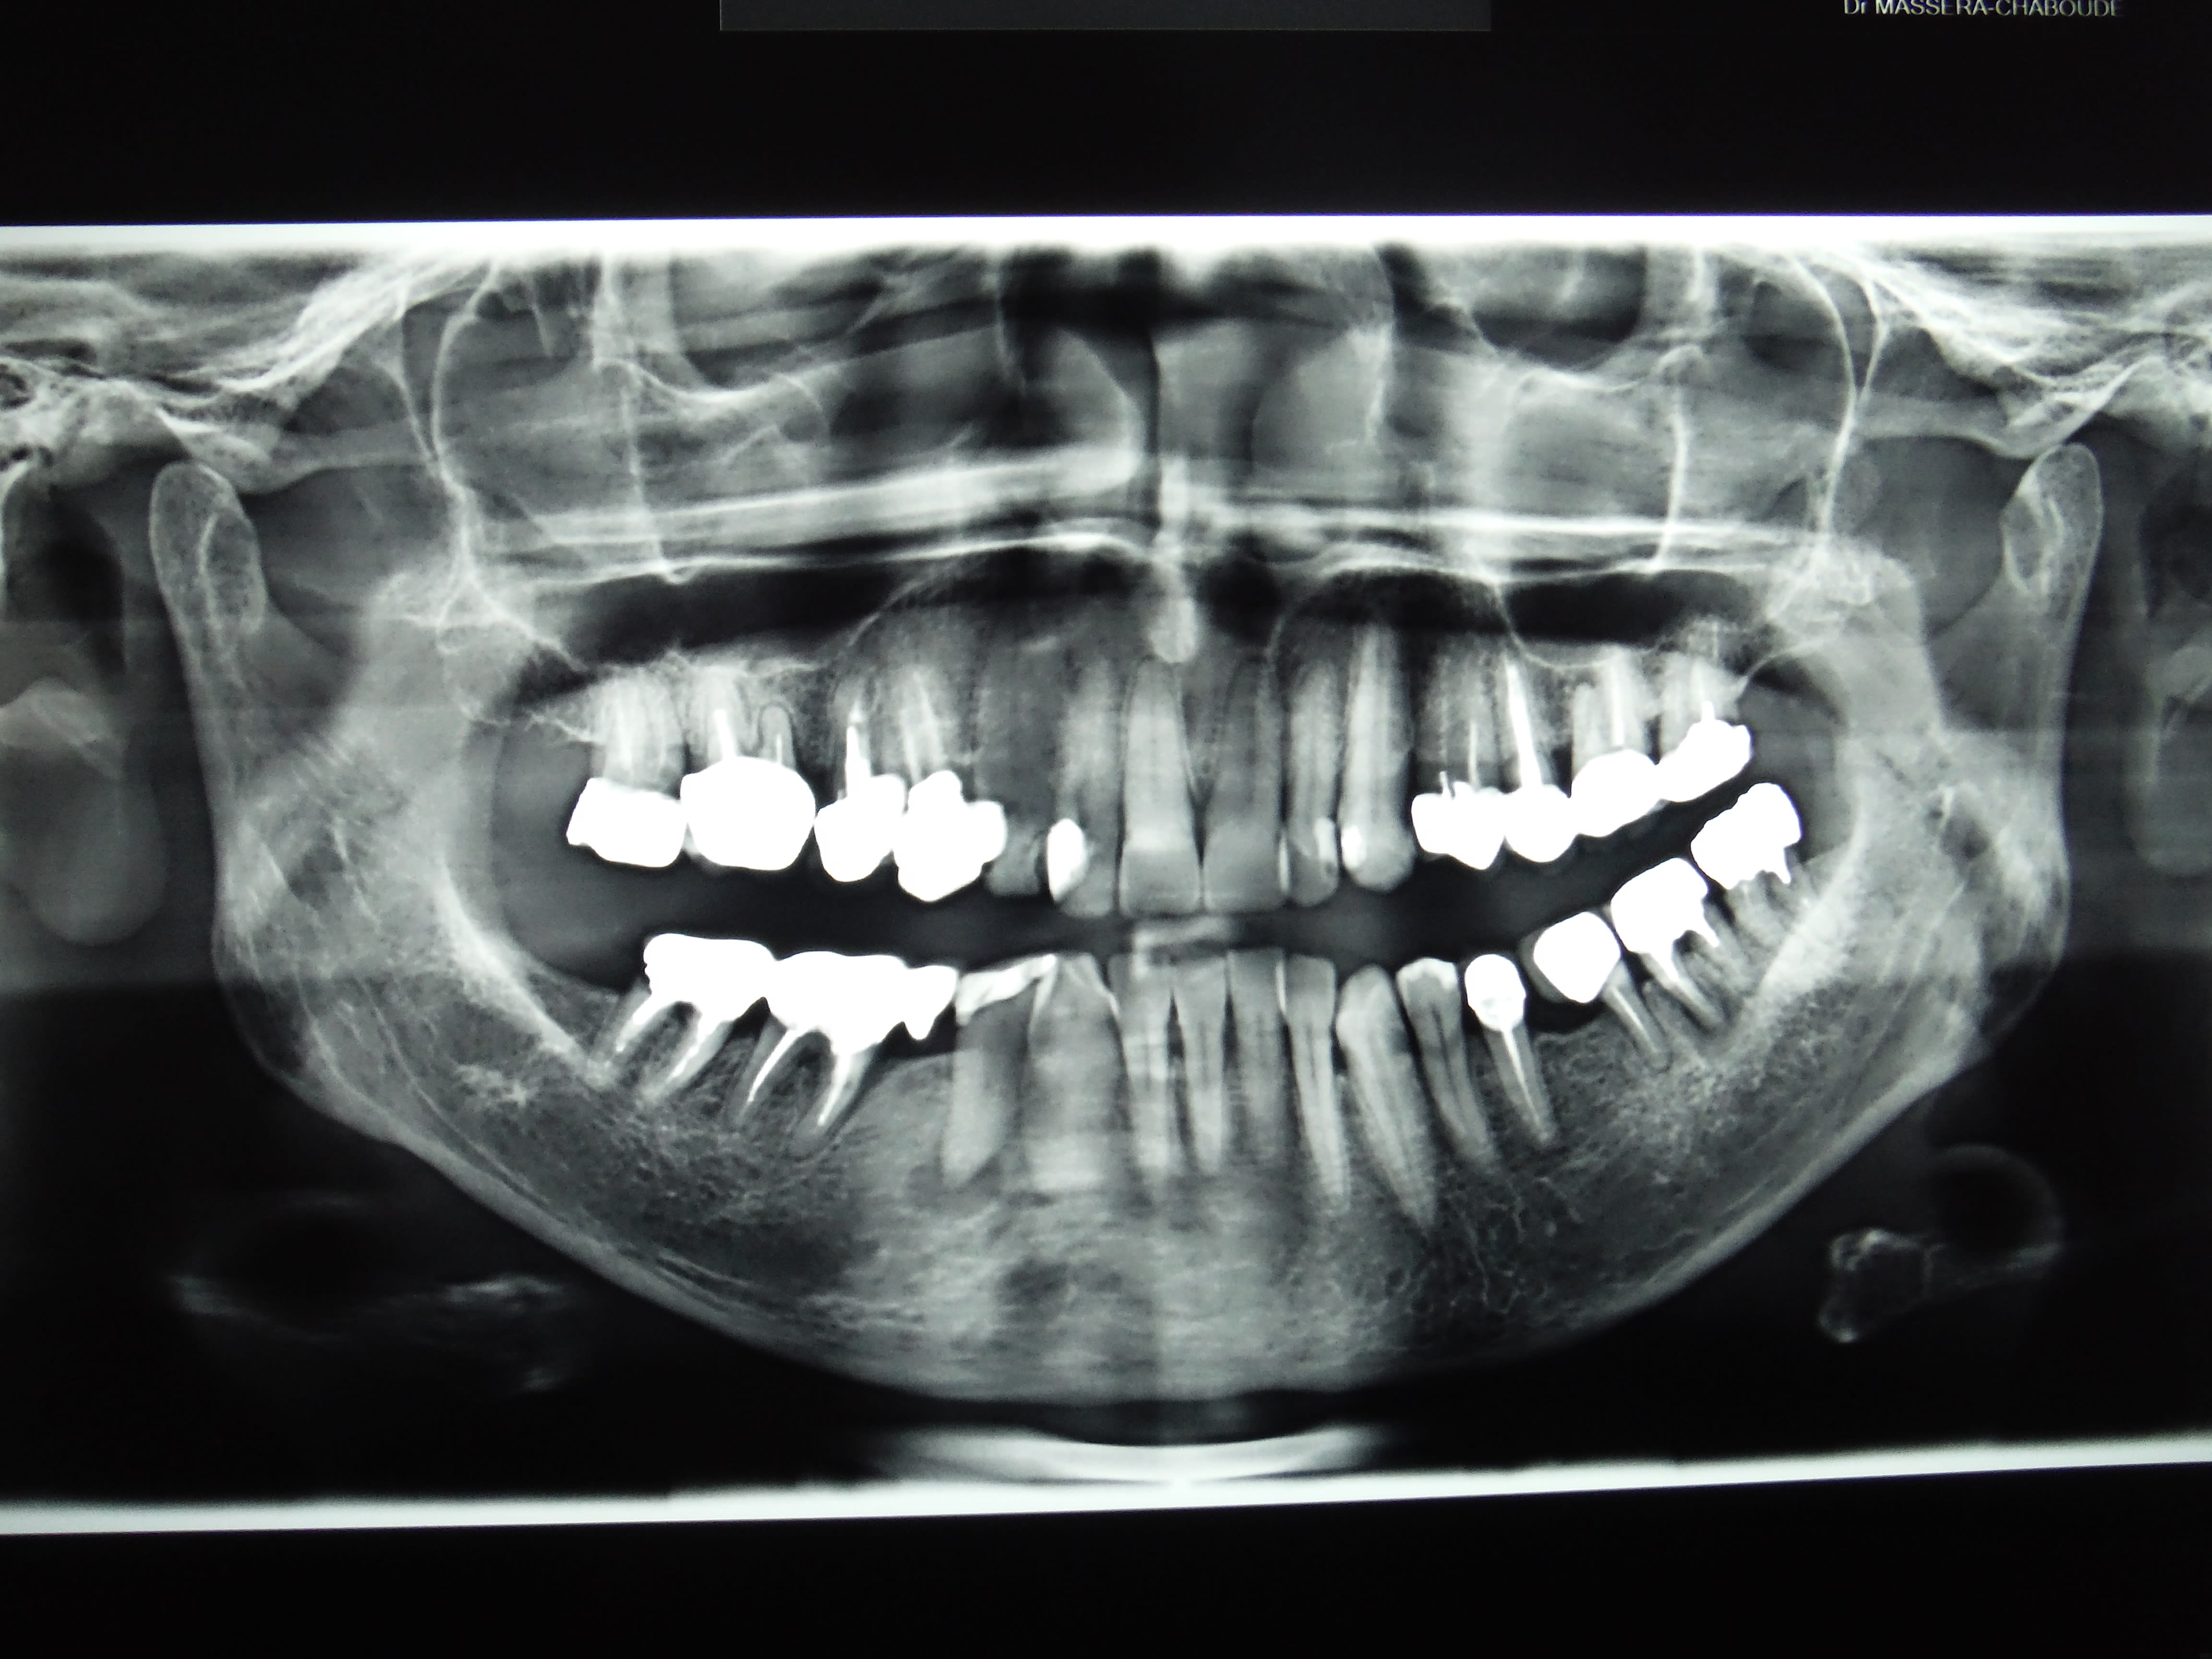

Ah la belle fixe et l'endo qui va avec.

Junior va être content, il y a même une nécrose, sous ce que l'on suppose être un onlay, un grand chelem.

Patient vu en urgence ( première fois) le 22/12 sur 15. ATB. je fais l'endo de 37 le 11 01 car j'avais le temps et remis le RTE de 15 la semaine suivante.

Ben figurez vous qu'il a pris rendez vous ailleurs ( sans annuler les RDV au cabinet) au motif que j'ai laissé l'infection sur 15 et qu'on ne prend rendez vous chez le dentiste que quand on a mal au dents et la 37 ne faisait pas mal ( la 15 non plus du reste après les ATB).

Mon pauvre garçon si tu savais En plus de la 15 tu as des traitements magnifiques sur 16 et 14. -)

D'ailleurs c'est un plaisir de ne pas avoir à les refaire un de ces 4 et de savoir que c'est un as de l'endo locale qui va s'occuper de toi. . -)))